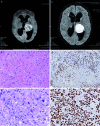

Results: 28 H3 K27M-mutant tumors were identified, with equal numbers of adults (13) vs. children (15). For adults, mean and median age was 52 years (range = 27 - 81 years), 2 decades older than a recently-published adult series. Tumors involved thalamic (adult = 7; pediatric = 7), spinal cord (adult = 4; pediatric = 2), pons (adult = 1; pediatric = 6), and hypothalamic (n = 1) sites. Other morphologies at presentation included pure GG (n = 3, pediatric) and PA (n = 1, adult). One adult and 1 pediatric patient each presented with leptomeningeal dissemination or developed leptomeningeal dissemination within 1 year after diagnosis, with transformation from PA or GG histology to glioblastoma. Mean survival was 9.3 (adults) vs. 8.9 (pediatric) months. Patients with tumors of other morphologies (GG, PA) did not enjoy extended survival.

Conclusion: H3 K27M-mutant tumors can affect patients at advanced ages, may show leptomeningeal dissemination at time of presentation, and "pure" GG or PA morphology is not rare. Regardless of patient age or tumor morphology, patients fare equally poorly. .